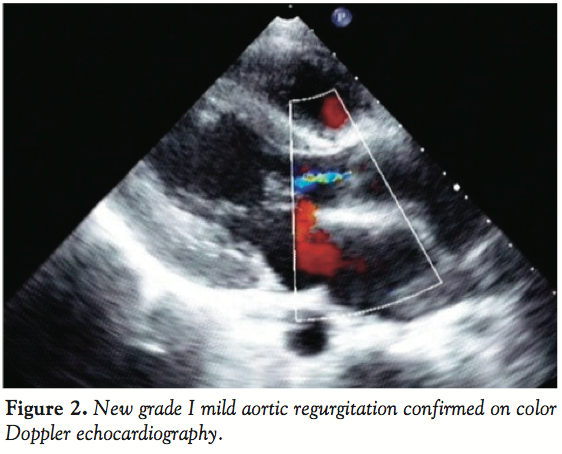

Catheterization revealed pulmonary artery pressure of 54/36 mmHg (mean of 42 mmHg), aortic pressure of 104/58 mmHg and Qp:Qs of 2:1. An ascending aortogram in anteroposterior projection confirmed the diagnosis (Figure 1A). The defect was crossed from the aorta with a Judkins right coronary catheter and an angled-tip, 0.035-inch glide wire, which was exchanged for a 300 cm long noodle wire (AGA Medical, Plymouth, Minnesota). Crossing of APW from pulmonary end was not attempted. A stable arteriovenous wire loop was established by snaring the noodle wire from the pulmonary artery with a 15 mm gooseneck snare (Microvena Corp., White Bear Lake, Minnesota) introduced from the femoral vein. A 6 Fr Amplatzer duct-occluder delivery sheath (AGA Medical) was introduced over the wire and placed across the defect into the ascending aorta. A 10/8 mm Amplatzer duct occluder with its attached delivery cable was then inserted through the delivery sheath, and its retention disk was deployed into the ascending aorta. The entire assembly was pulled back until the aortic disk blocked the APW from the aortic side.

After confirming precise position of the device on transthoracic echocardiography and control angiography, the rest of the device was deployed on the pulmonary arterial side, by withdrawing the delivery sheath. Post-release angiogram revealed no residual shunt. However, there was new grade I mild AR (Figure 1B) that was also confirmed on color doppler echocardiography (Figure 2). Clinically no murmur was audible and aortic pulse pressure had decreased as well as pulmonary artery pressure (Aortic pressure 112/72 mmHg; pulmonary artery pressure 40/25 mmHg; mean 33 mmHg). As the defect was remote from aortic valve and there was no impingement on it, the result was accepted. On follow-up at 3 months and 6 months, patient was asymptomatic. Importantly, there was a progressive decrease in the grade of AR from mild to only trivial grade at 6 months (Figure 3).